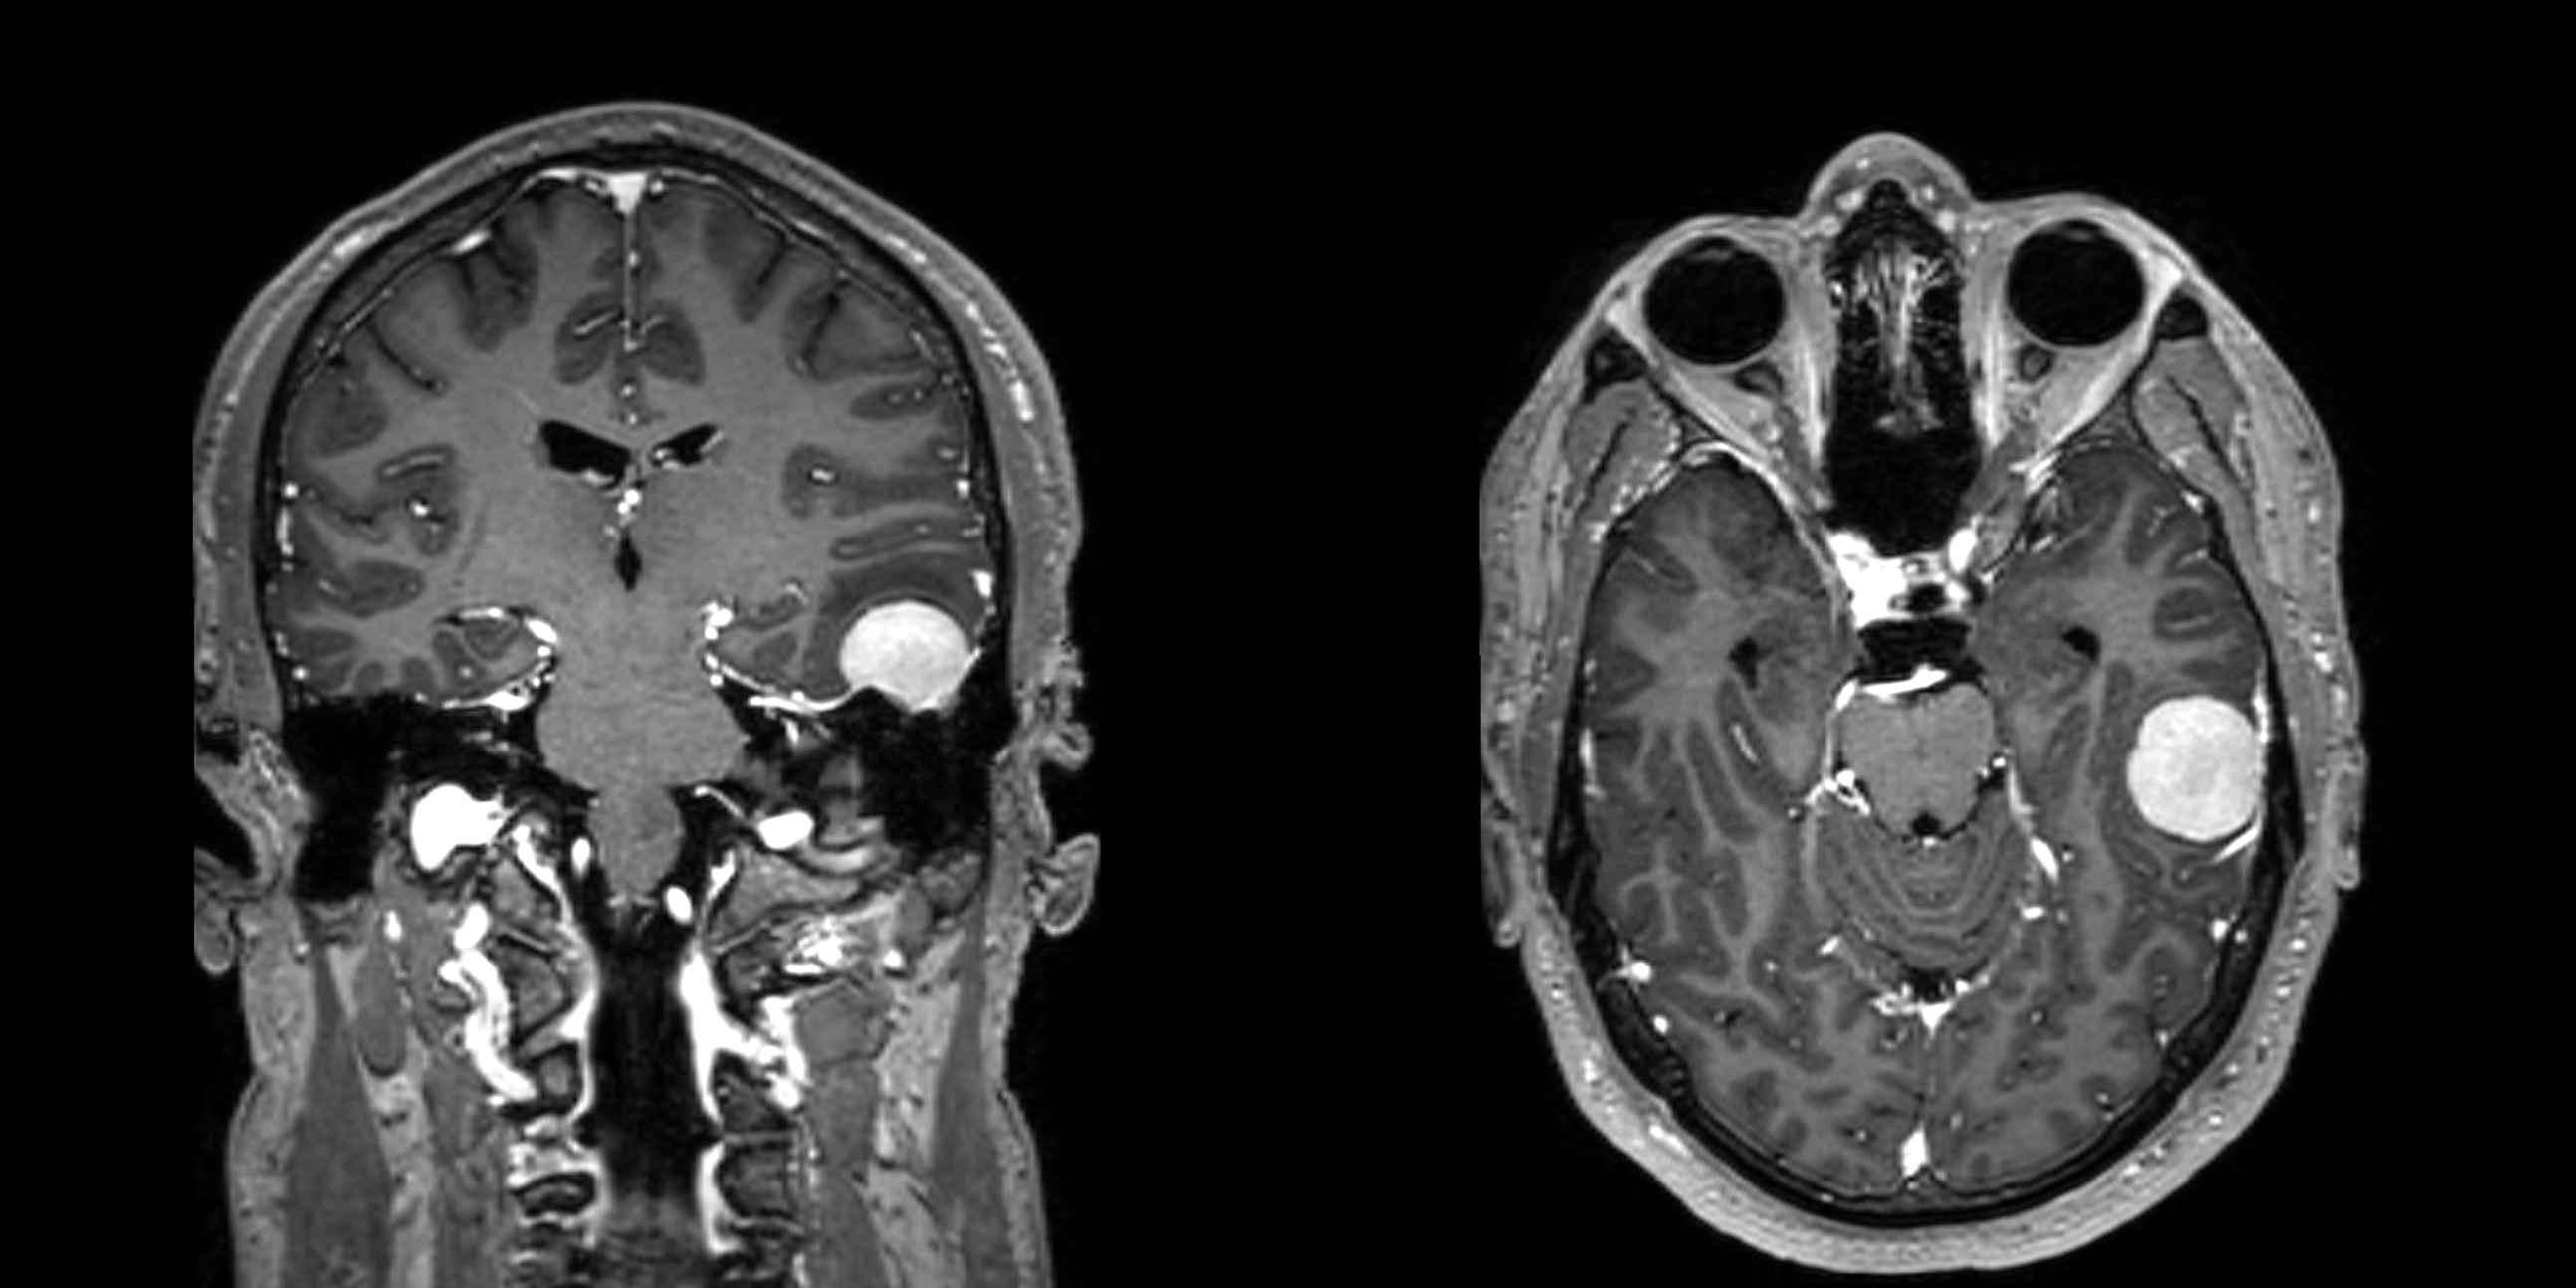

No significant differences were observed between the OCR and RTX treatment groups at 2, 4, and more than 4 years, although both groups showed a progressive accumulation of immune marker deficiencies over time (Figure 1). By year 4 of treatment, deficiencies were most common in IgM (26-31%), followed by IgG (12-13%), IgA (4-7%), lymphocytes (5.3-5.4%), and neutrophils (0-1.7%).

Screen shot 2025 05 06 at 8.17.56 pm Noun slideshow grey Screen shot 2025 05 06 at 8.18.17 pm Screen shot 2025 05 06 at 8.18.33 pm

Figure 1. Prevalence of immune marker deficiencies across treatment duration.

Bar charts showing the percentage of OCR- versus RTX-treated patients developing new immunoglobulin and cell count deficiencies at three time points (2, 4, and >4 years of treatment).

Survival analysis reveals that RTX is associated with significantly higher risks of developing IgM deficiency (HR=1.6, p=0.016, 95% CI 1.09-2.34) and IgA deficiency (HR=2.38, p=0.048, 95% CI 1.01-5.63) compared to OCR, despite similar cross-sectional prevalence rates. Linear regression analysis confirms RTX causes significantly faster IgM depletion (p=0.0044 for slope difference, p < 0.05 in mixed model, Figure 2).

Igm trajectories Noun slideshow grey Igg trajectories Iga trajectories Neutrophil trajectories Lymphocyte trajectories All parameters survival curves

Figure 2.  Longitudinal immune marker trajectories by treatment regimen

Spaghetti plots show individual patient data (thin lines) and demonstrate considerable inter-patient variability. Treatment-specific regression lines (thick lines, with shading that demonstrates 95% CI) show overall trends. Deficiency threshold is represented by red dotted lines. Kaplan-Meier curves depict survival analysis.